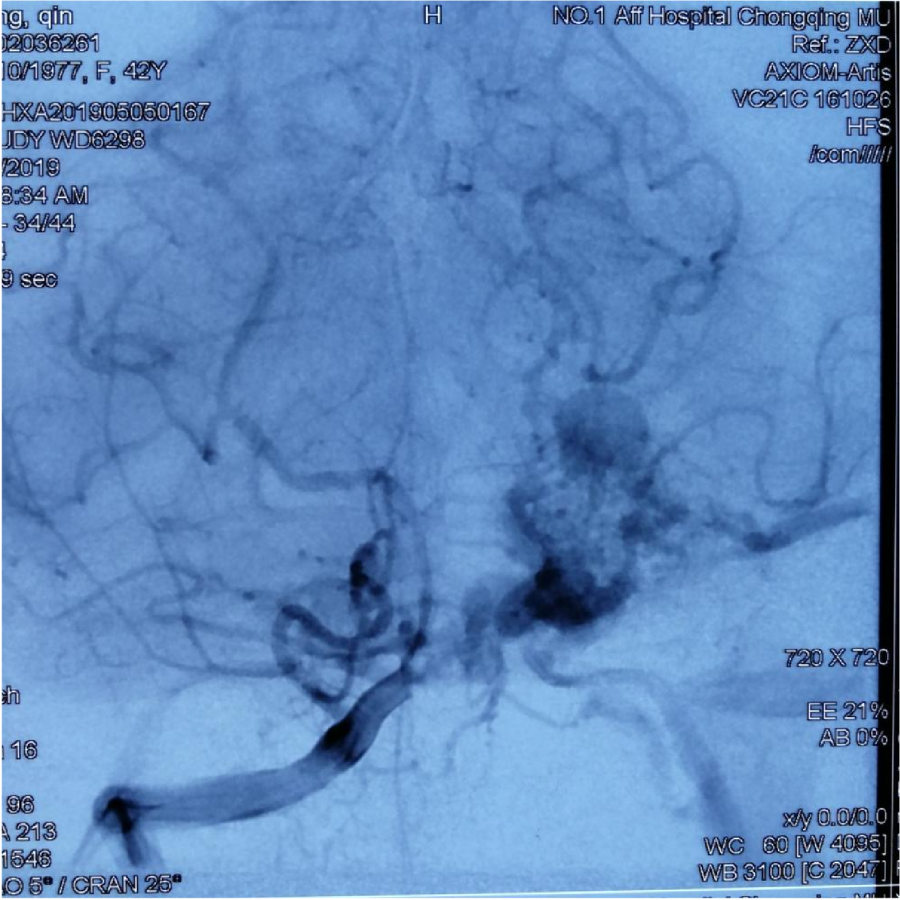

第⼀次DSA显⽰PICA供⾎

引流⾄⼄状窦

小脑后下动脉、小脑前下动脉参与供⾎

本次⼊院⾏DSA检查:PICA供⾎区有畸形⾎管团,引流到横窦